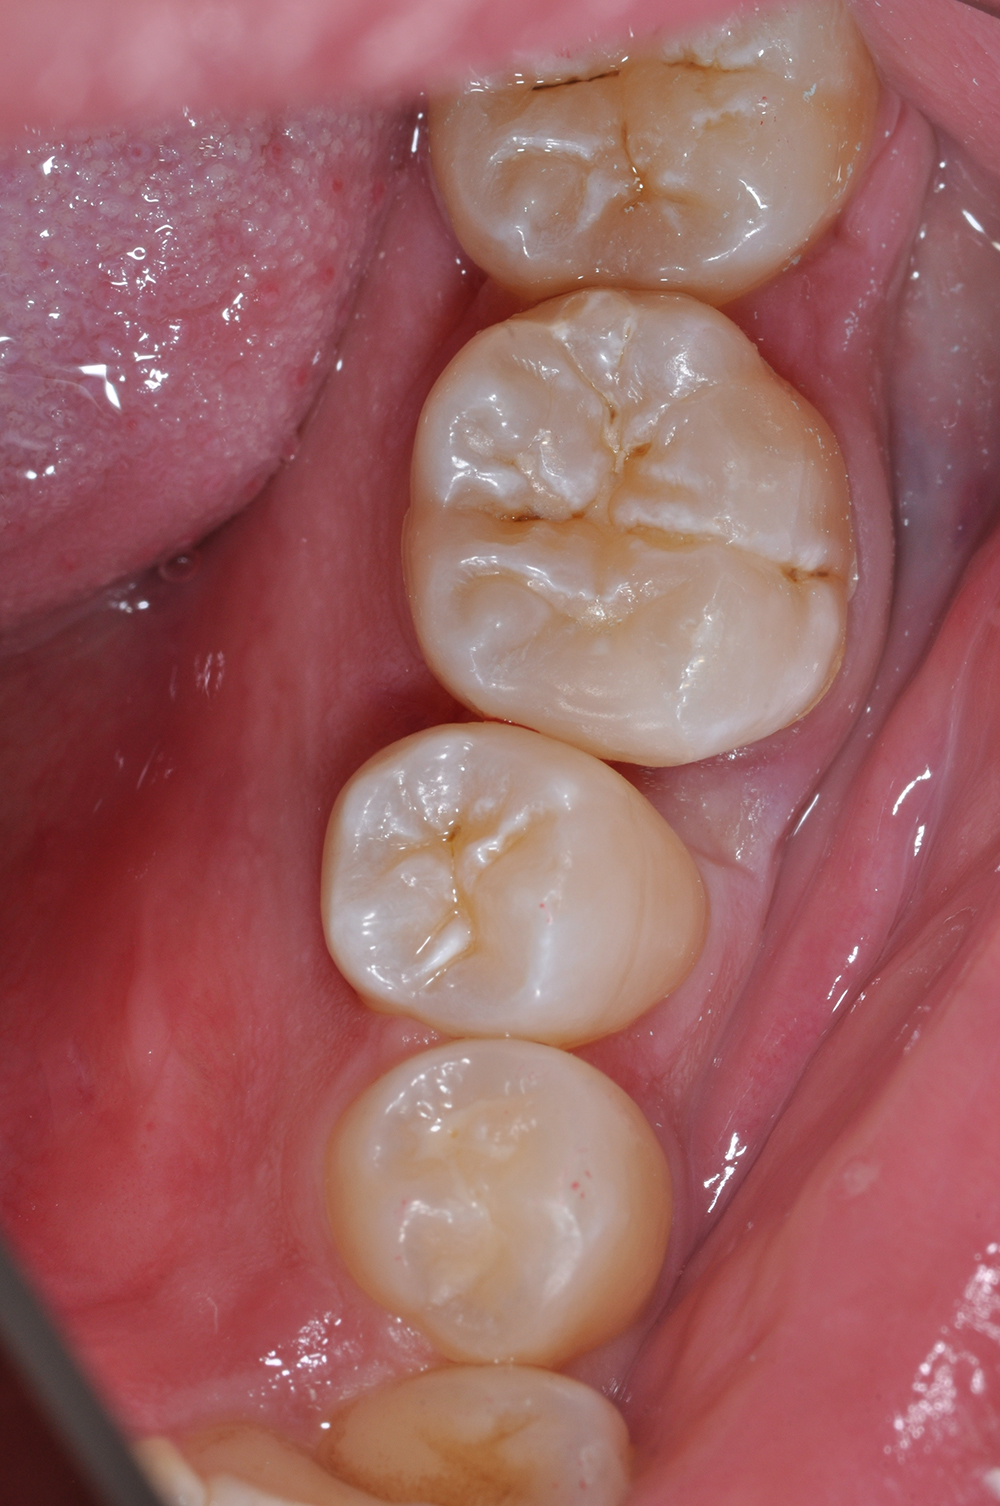

術前

術後

世代・性別

30代女性

主訴

歯がしみる時がある

治療内容

セラミックインレー

治療期間

2回

治療費

66,000円(税込)

治療のリスク

強い咬合力や衝撃によって、欠けたり割れたりすることがある